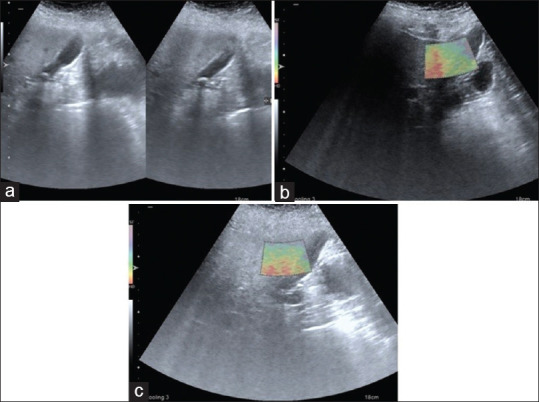

图 7

(a) 胆囊结石的超声图像(b 和 c)胆囊体部和颈部两处粘连 E2 的 VTI 图像。VTI:虚拟触摸成像